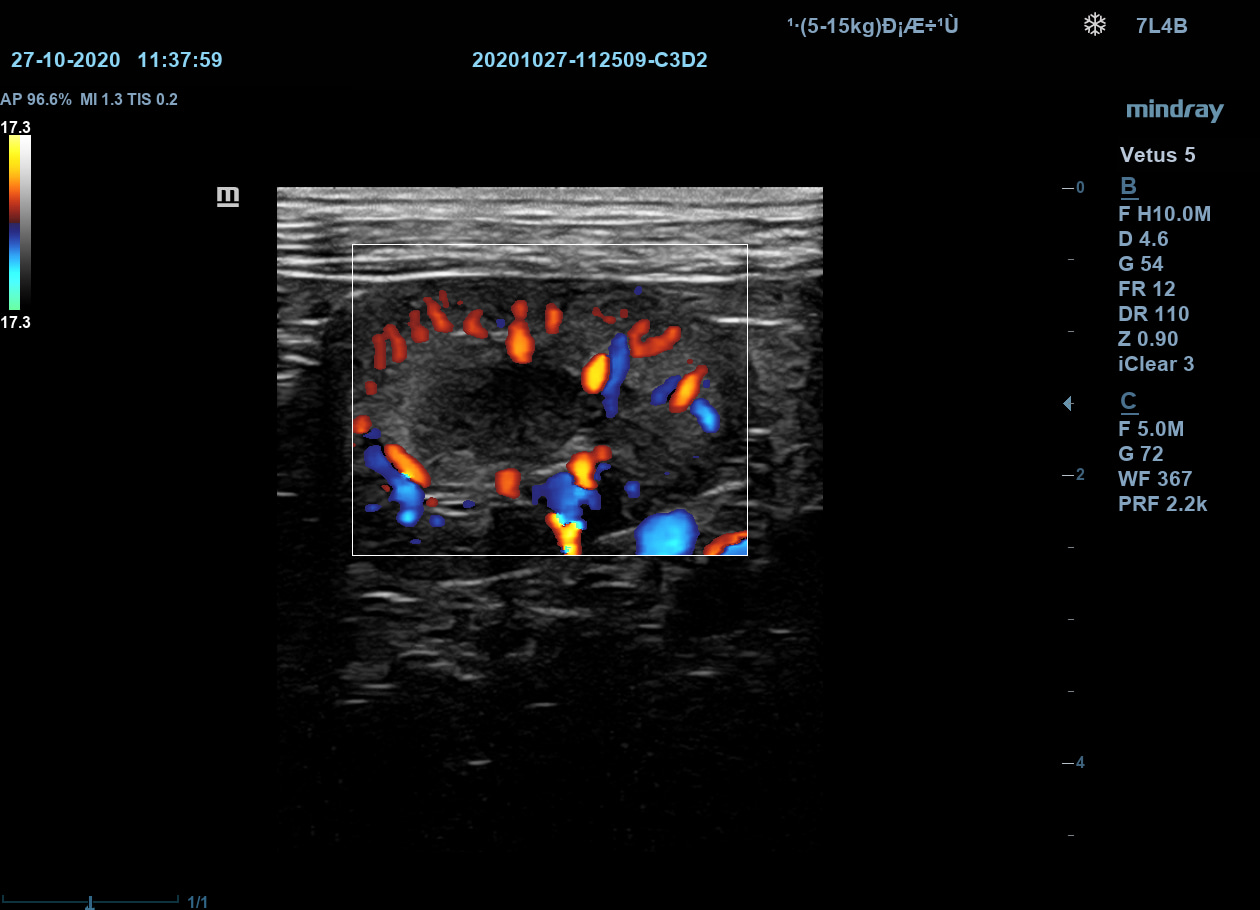

Датчики с технологией ComboWave

По сравнению с традиционными датчиками, в датчиках с технологией ComboWave используется новый тип композитного пьезоэлектрического материала. Благодаря свойствам этого материала, оптимизируется акустический спектр и подавляются акустические шумы.

Датчики с технологией ComboWave

По сравнению с традиционными датчиками, в датчиках с технологией ComboWave используется новый тип композитного пьезоэлектрического материала. Благодаря свойствам этого материала, оптимизируется акустический спектр и подавляются акустические шумы.